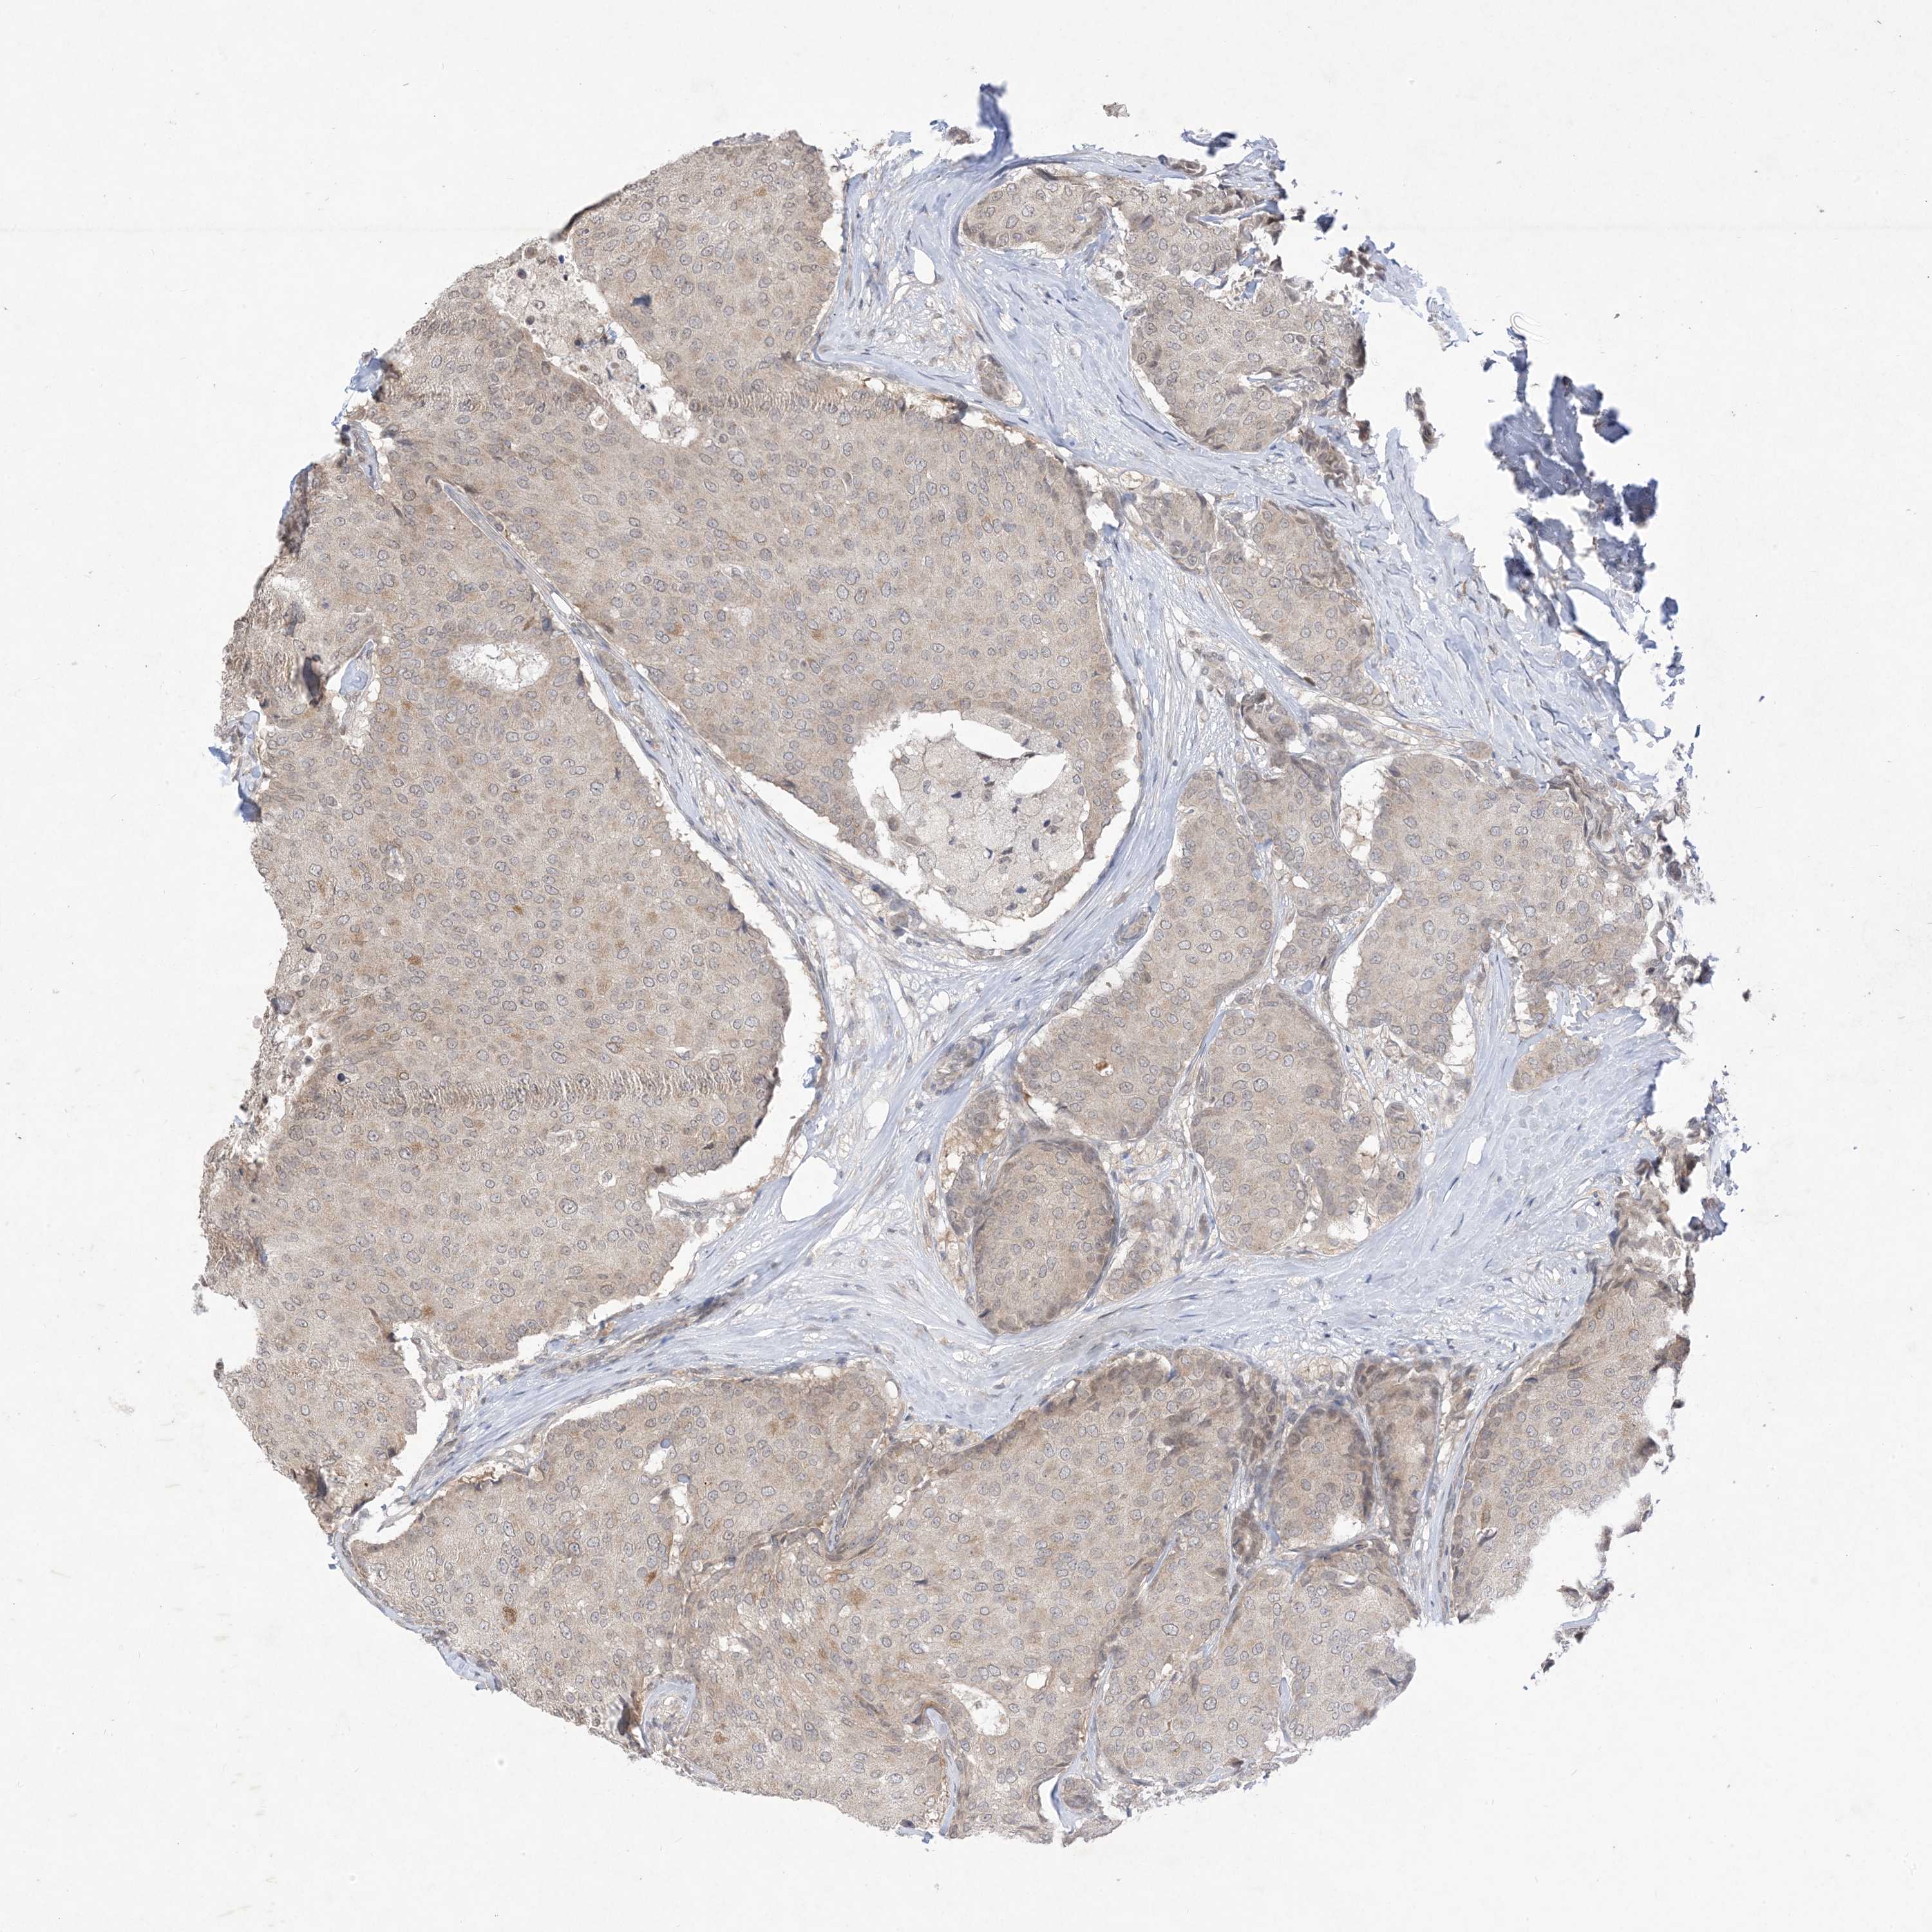

CANCER BREAST CANCER Show tissue menu

BRCA TCGA BRCA VALIDATION PROTEIN EXPRESSION